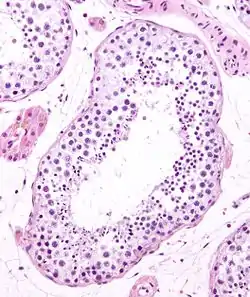

Seminiferous tubule

Seminiferous tubule in cross-section (large tubular structure – center of image) with sperm (black, tiny, ovoid bodies furthest from the outer edge of the tubular structure). H&E stain.

Seminiferous tubules are located within the testicles, and are the specific location of meiosis, and the subsequent creation of male gametes, namely spermatozoa.

The epithelium of the tubule consists of a type of sustentacular cells known as Sertoli cells, which are tall, columnar type cells that line the tubule.

In between the Sertoli cells are spermatogenic cells, which differentiate through meiosis to sperm cells. Sertoli cells function to nourish the developing sperm cells. They secrete androgen-binding protein, a binding protein which increases the concentration of testosterone.